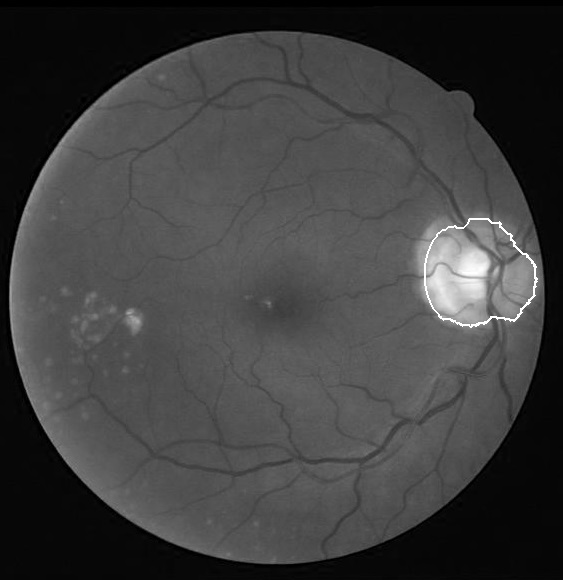

We applied our algorithm on 40 images of DRIVE dataset111http://www.isi.uu.nl/Research/Databases/DRIVE/and 50 images of Khatam database222Images of this database are gathered by Khatam-Al-Anbia eye hospital, Mashhad, Iran. In both datasets the optic disk boundary is hand labeled by an ophthalmologist as ground truth. Fig. 3 and Fig. 4 show our results on the DRIVE and Khatam databases respectively. The results show that our algorithm is robust to changing illumination and also to abnormal retinal images. The result on the second image of Khatam dataset (Fig. 3) shows that our algorithm can distinguish between parapapillary atrophy boundary and optic disk boundary.

In the first step, we need to define a window with the center of the optic disk. To accomplish this task, the center of the obtained region from the optic disk localization step is modified. The obtained region from the optic disk localization step is located at the temporal part of the optic disk. The reason is that this part is brighter than the other parts of the optic disk (superior, inferior and nasal parts. Fig 2), so the center of this area can approximate the center of optic disk height. But, this point can be the center of optic disk width if only the brightest part of the temporal side is close to the optic disk vessels. Therefore, by the information obtained from the vessel segmentation step, we adjust this point so that it gets close to the vessel. This point is used as the first estimation of optic disk center.

There are some characteristics which can be used to extract the optic disk. Sometimes, the optic disk area is brighter than its surrounding and it can be seen as a disk and in other images it appears as a hollow ring. Moreover, the optic disk part located on the temporal side is often more visible and brighter than the nasal part.